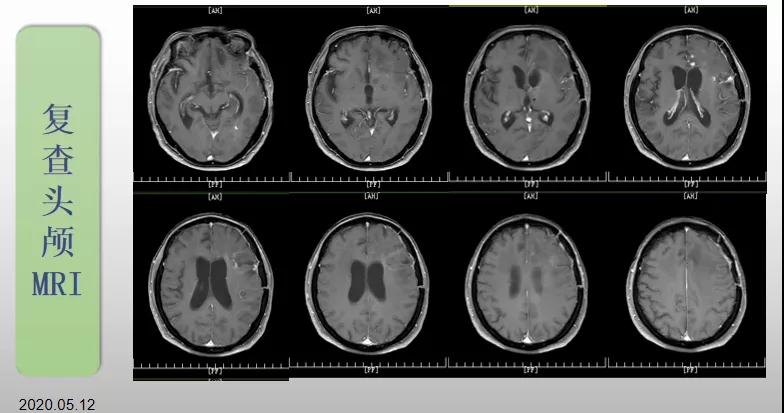

綜合治療 電場(chǎng)治療助70歲患者回歸正常生活

70歲的郝女士去年曾在外院查出“左額島葉”膠質(zhì)母細(xì)胞瘤(WHO Ⅳ級(jí)),并做了左側(cè)額島葉占位性病變切除術(shù)。術(shù)后進(jìn)行了同步放化療。由于治療條件有限,郝女士慕名來(lái)到我院就診。賀世明主任率領(lǐng)醫(yī)護(hù)團(tuán)隊(duì)立即為郝女士進(jìn)行了全面的檢查,決定為其進(jìn)行綜合治療 電場(chǎng)治療。經(jīng)過(guò)三個(gè)多月的綜合治療,患者復(fù)查頭顱MRI病變較前明顯縮小。出院時(shí),郝女士神志清醒,睡眠飲食正常,說(shuō)話(huà)很流利?!拔沂翘芍M(jìn)來(lái)的,現(xiàn)在不用人攙扶,自己就可以走出病房了?!焙屡坷t(yī)護(hù)人員的手說(shuō)。